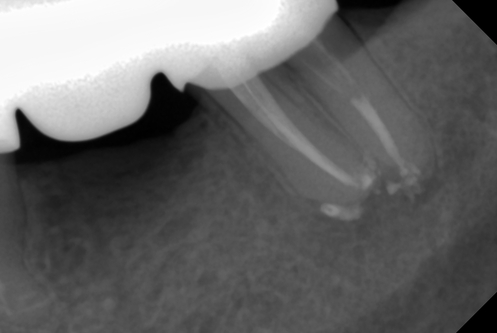

В стоматологической клинике "5 Принципов" в Симферополе мы гордимся тем, что каждый пациент получает индивидуальный подход и безупречный результат в области эндодонтического лечения под микроскопом. Наши специалисты применяют современные цифровые технологии, микропроцессорные и нейромодуляционные инструменты, что позволяет достичь максимальной точности и минимального дискомфорта. В портфолио клиники — широкий спектр кейсов: от первичной диагностики пульпита до сложной ретенированной резорбции и повторной эндодонтии. Мы беремся за зубы любых степеней сложности: от моляра до резцов, используя щадящие концевые инструменты и безболезненные методы постоянной анестезии. Все процедуры проходят под увеличением, что обеспечивает точное удаление инфицированной ткани и сохранение естественной анатомии зуба.Особое внимание мы уделяем постпроцедурному наблюдению: контроль за герметичностью заполнения корневых каналов, профилактические рекомендации и возможная корректировка плана лечения при необходимости. В "5 Принципах" мы разумно сочетаем комфорт, эстетическую привлекательность и долгосрочную функциональность. Результат — здоровые зубы, уверенная улыбка и спокойствие наших пациентов в Симферополе. Запишитесь на консультацию и убедитесь сами в нашем подходе к качественному эндодонтическому лечению.